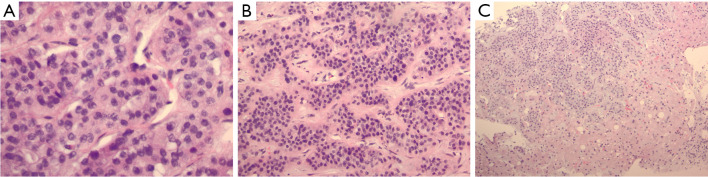

Case description: We present a rare case of HHM secondary to cholangiocarcinoma. This case presents a rare case of HHM due to cholangiocarcinoma with an atypical presentation in a 55-year-old female. This patient presented with abdominal swelling and severe hypercalcemia prompting evaluation for a possible gastrointestinal source and was found to have HHM due to cholangiocarcinoma. She was treated for her hypercalcemia medically, however due to the extent of her disease she was unable to undergo surgery. Chemotherapy was not considered during her initial presentation as she originally had a malignancy of unknown primary. Ultimately, shortly after her initial presentation, the patient passed at another hospitalization 36 days after her initial presentation.